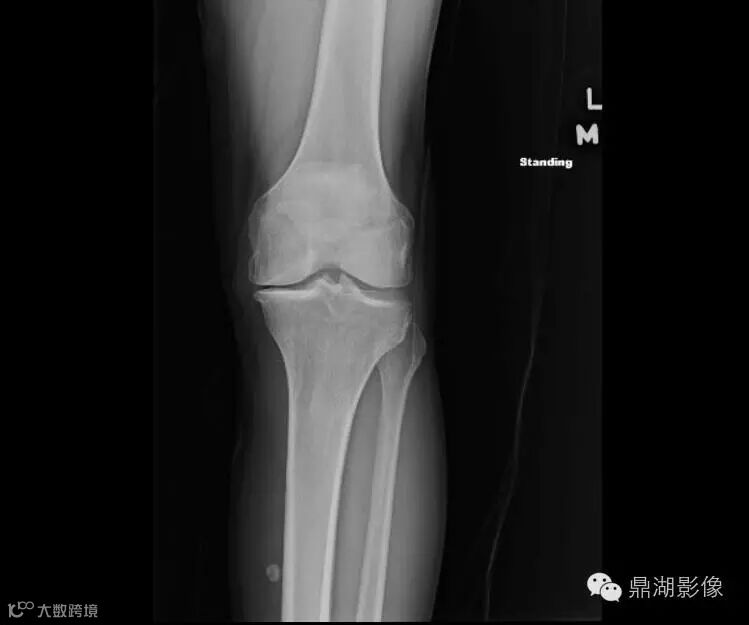

An 81-year-old man presents to the emergency department with pain and swelling of the left knee and calf. Left knee radiographs were obtained

1.1 What pertinent findings are demonstrated on the images below?

A. Osteoarthrosis

B. Calcification within the posteromedial aspect of the upper calf soft tissues

C. Avulsion fracture suggesting underlying ligamentous injury

D. Chondrocalcinosis

Ok ,let's go on,the correct answer is ABD

解析:A.Osteoarthrosis is correct. There is joint-space narrowing, osteophyte formation, and subchondral sclerosis.

B. Calcification is seen within the posteromedial aspect of the upper calf soft tissues.

C.An avulsion fracture is not present to suggest an underlying ligamentous injury.

Frontal view of the left knee demonstrates joint-space narrowing (yellow arrow), osteophyte formation (red arrow), and chondrocalcinosis (blue arrow). There is a calcified body (white arrow) within the inferior recess of a dissecting Baker cyst.